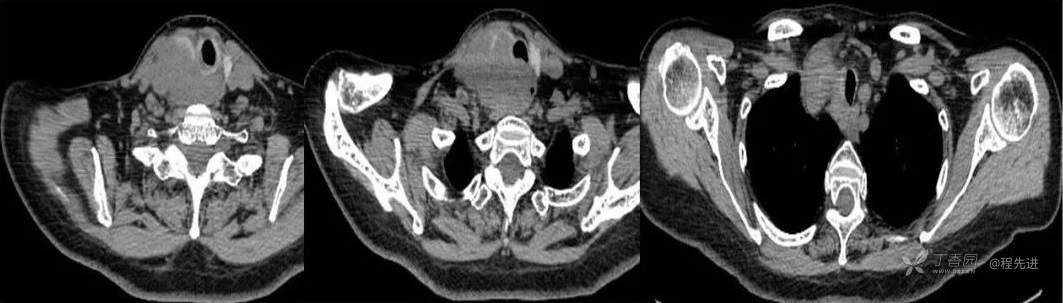

CT

平扫